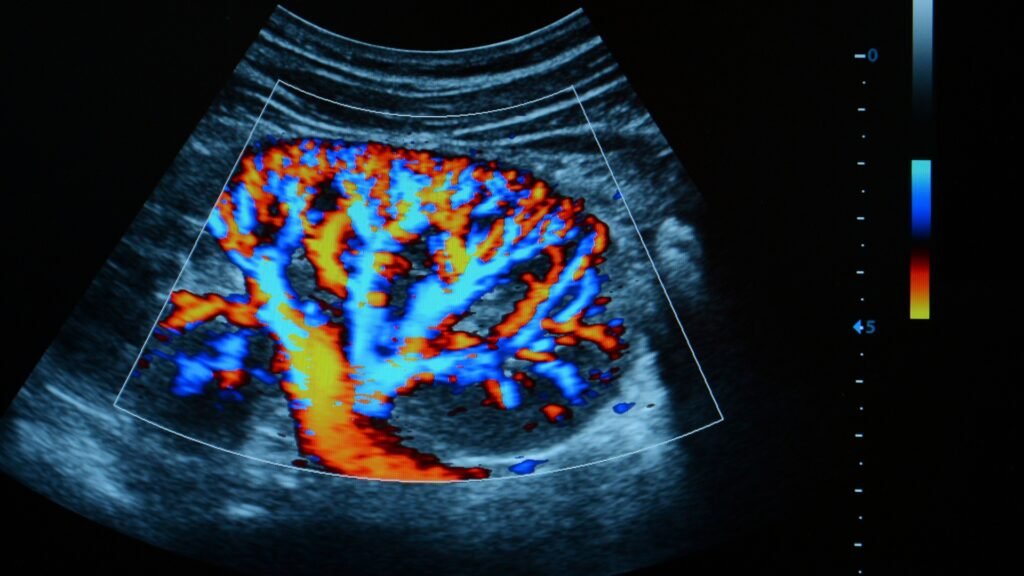

Esse exame utiliza ondas sonoras para gerar imagens detalhadas das artérias principais no pescoço. A técnica Doppler adiciona uma codificação de cores às imagens, permitindo visualizar o fluxo sanguíneo em tempo real. Isso ajuda a identificar obstruções, tromboses e outras irregularidades, essencial para pacientes com risco de acidente vascular cerebral (AVC) ou doenças arteriais obstrutivas.

- Avaliação Detalhada do Fluxo Sanguíneo: Fornece informações sobre a velocidade e a direção do fluxo nas artérias cervicais, fundamentais para um diagnóstico preciso.

- O que o exame pode revelar sobre a saúde das minhas artérias? O Doppler colorido pode detectar estreitamentos (estenoses), bloqueios (tromboses) e outras anomalias no fluxo sanguíneo das artérias carótidas e vertebrais, proporcionando informações críticas para a prevenção de AVCs e outras complicações vasculares.